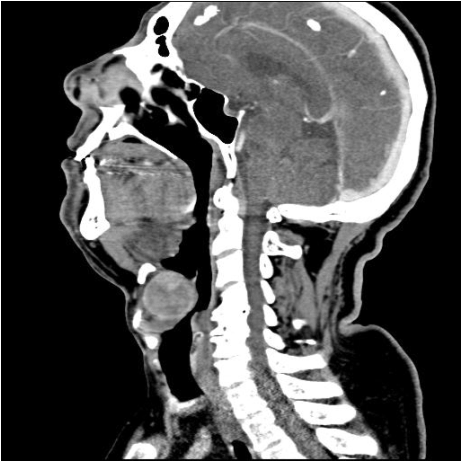

A 66-year-old male presented to our clinic with a two year history of progressively disabling dysphonia which had disrupted his career as a cantor. His physical examination was normal. Fiberoptic laryngoscopy revealed a bulging mass in the left paraglottic space extending to the vallecula and displacing the left vocal cord. A computed tomography (CT) scan was performed which demonstrated a 3.5 cm well delineated submucosal mass, located in the left paraglottic space and extending to the pre-epiglottic space and left vallecular region (Figures 1, 2). There was no evidence of cartilaginous destruction.

Figure 1: A sagittal post contrast CT scan showed a mass in the pre-epiglottic space at the level of the vallecula.

Tumor presentation depends on the exact location of the mass. There are no specific clinical signs, and symptoms are usually progressive. When the origin is in the larynx, the most common symptoms are hoarseness, breathing difficulties, foreign body sensation, cough and throat clearing. [4] CT scan shows a submucosal dense homogeneous enhancement of the mass on post contrast studies. CT imaging is essential to rule out adjacent bony or cartilaginous involvement, which usually does not occur with solitary fibrous tumors. [2]